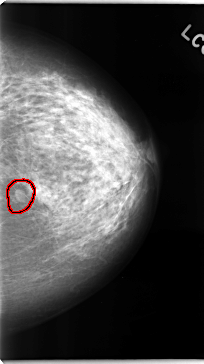

FILE: C_0102_1.RIGHT_CC.OVERLAY

TOTAL_ABNORMALITIES 1

ABNORMALITY 1

LESION_TYPE MASS SHAPE IRREGULAR MARGINS SPICULATED

ASSESSMENT 5

SUBTLETY 5

PATHOLOGY MALIGNANT

TOTAL_OUTLINES 1

BOUNDARY